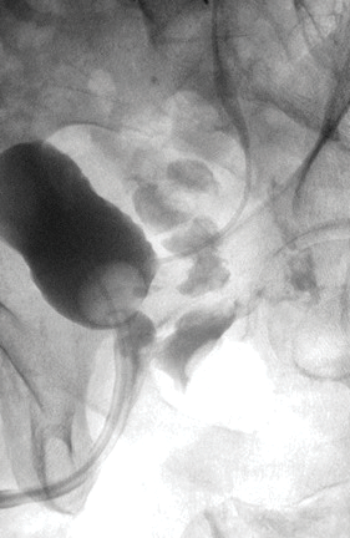

1. What is this investigation and what is demonstrated?

A cystogram demonstrating a recto-urethral fistula. Ureteric stent is visible.